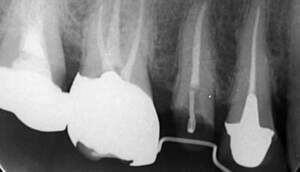

レントゲンで見ても、右上2では歯質が歯肉縁上にのこっていない。しかし歯根は長いのでMTMの適応症例です。

| 治療前で歯根が長いのがわかります。歯根がある程度長く無いと、MTMは行えません。 | MTM終了時のもの。フックが上の金属に接している。また根尖に透過像があるが、歯が動いた証拠です。 |

治療前で歯根が長いのがわかります。歯根がある程度長く無いと、MTMは行えません。 |

MTM終了時のもの。フックが上の金属に接しています。また根尖に透過像があるが、歯が動いた証拠です。 |